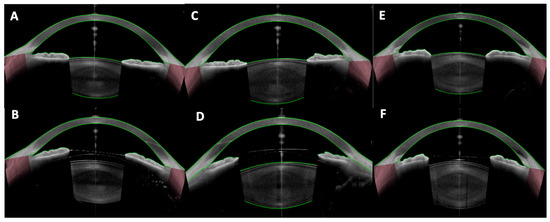

Background and Objectives: Optic disc drusen (ODD) can mimic papilledema and are linked to structural crowding, microvascular change, and visual-field loss. We synthesized structural/microvascular differences, functional status and change, diagnostic...